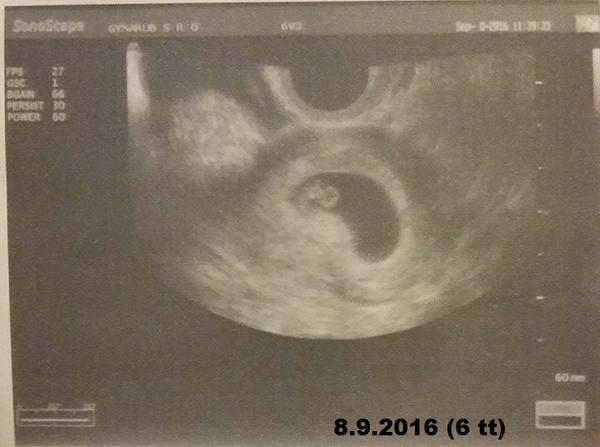

Baby ahaaa 🙂 dnes sme mali krásne blikajúce srdiečko a podľa sona som 6 tt 🙂